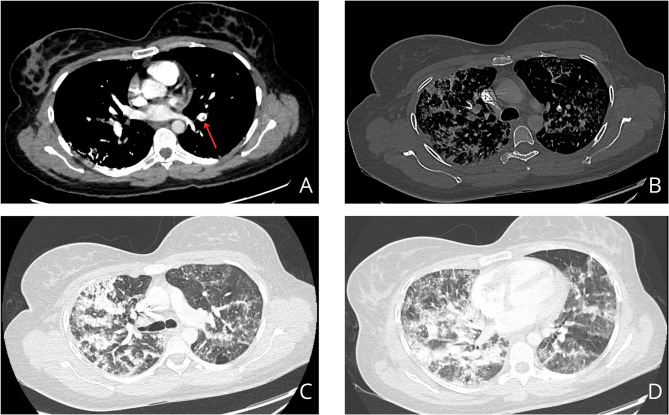

Case presentation: A 31-year-old woman developed respiratory failure 24 h after radiological embolization of pelvic varices. Glue embolization was detected during the intervention and was confirmed on a chest CT scan showing multiple bilateral hyperdense elements up to sub-pleural regions. The patient developed respiratory symptoms 24 h after the procedure, progressively worsening with oxygen requirement up to 6 L/min. A follow-up chest CT angiography showed a thrombotic pulmonary embolism. Treatments included curative anticoagulation, antibiotherapy, corticosteroids, and oxygen, leading to improvement after 10 days of treatment.